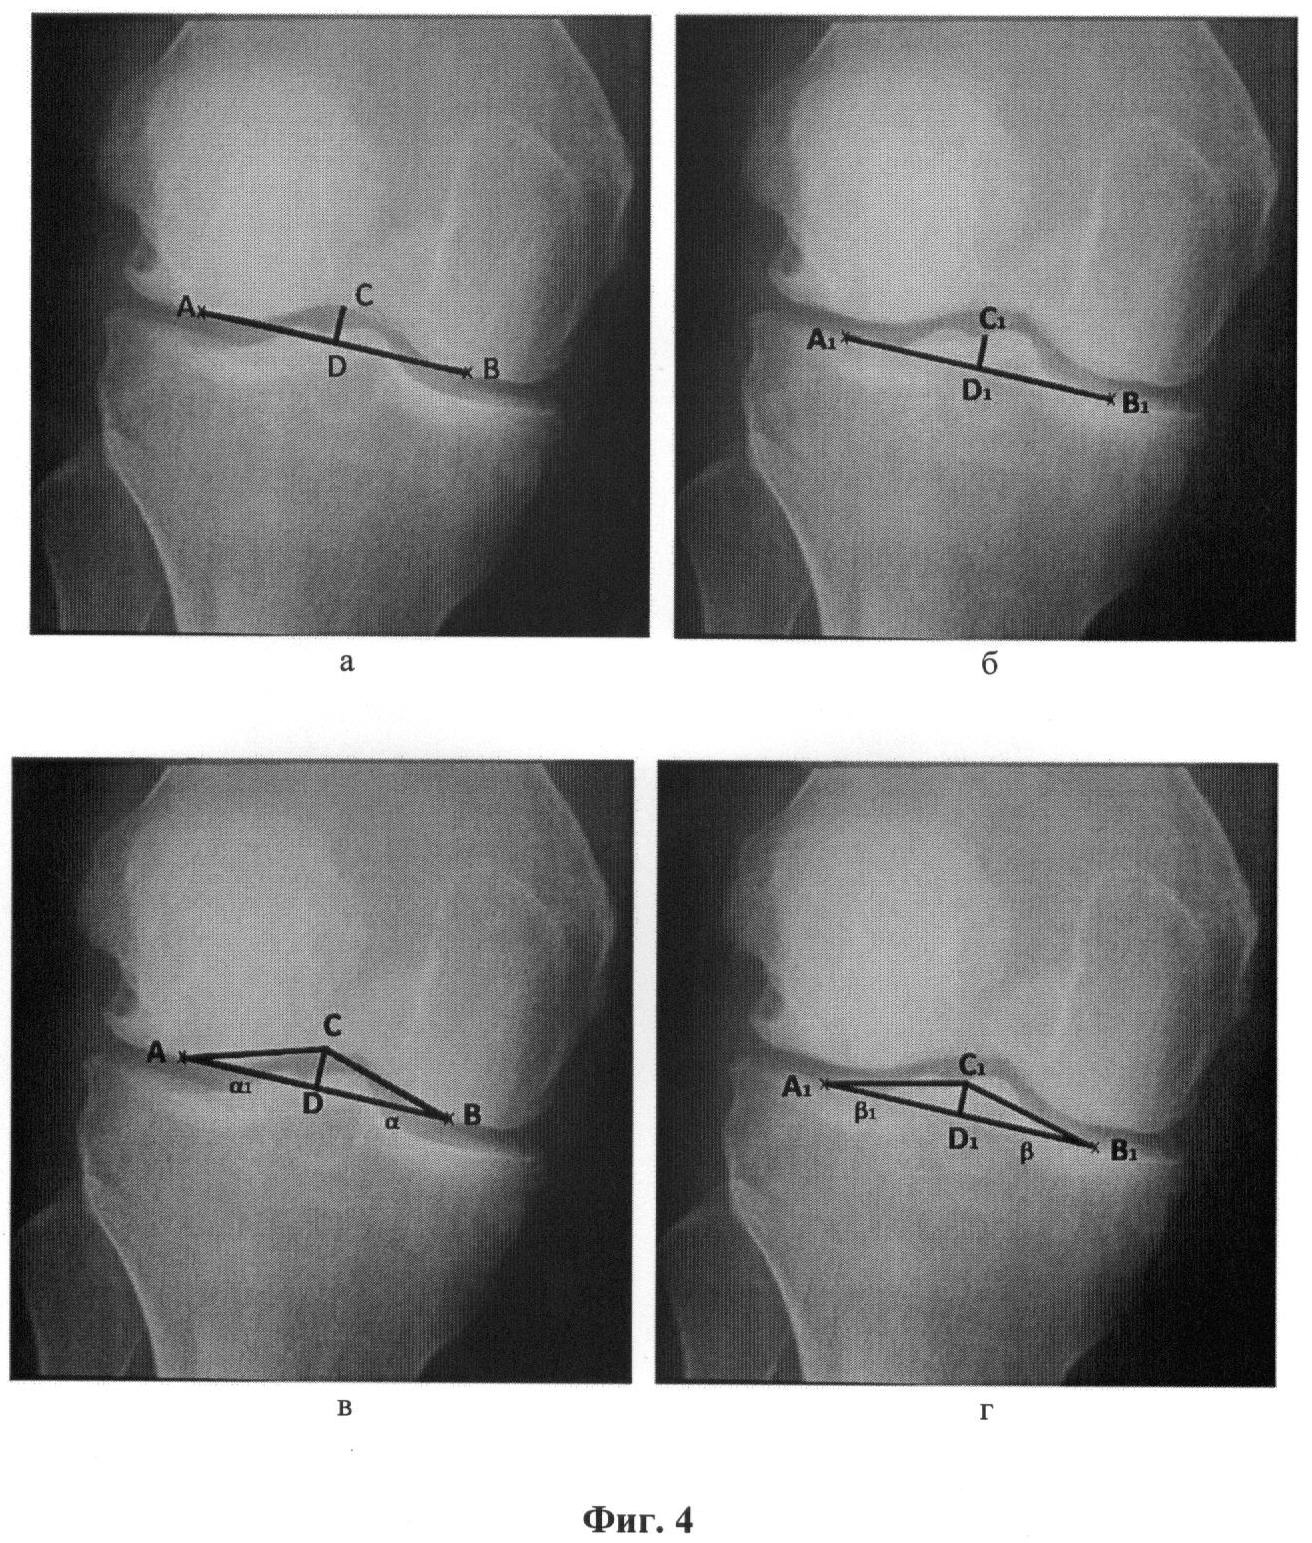

Фиг.3 – рентгенограмма левого коленного сустава пациента К., 30 лет, а – точки отсчета и линии для определения индексов межмыщелковой ямки; б – точки отсчета и линии для определения индексов межмыщелкового возвышения; в – точки отсчета и треугольник для определения углов мыщелков бедренной кости; г – точки отсчета и треугольник для определения углов мыщелков большеберцовой кости.

Пример 1. Рентгенограмма коленного сустава в переднезадней проекции пациентки К., возраст 30 лет. При рентгенологическом исследовании здорового коленного сустава (фиг.3) получены следующие рентгенометрические данные: ИМЯ составлял величину 4,4; ИМВ равен величине 5,4. Сопоставляя полученные результаты со средним индексом, полученным при измерении нормальных коленных суставов, констатируем, что геометрия мыщелков коленного сустава пациентки К. в пределах нормы и не имеет признаков аномалии возрастного развития.

Об этом же свидетельствуют величины углов , 1 – 24° на бедренной и величины углов , 1 – 20° большеберцовой костей.